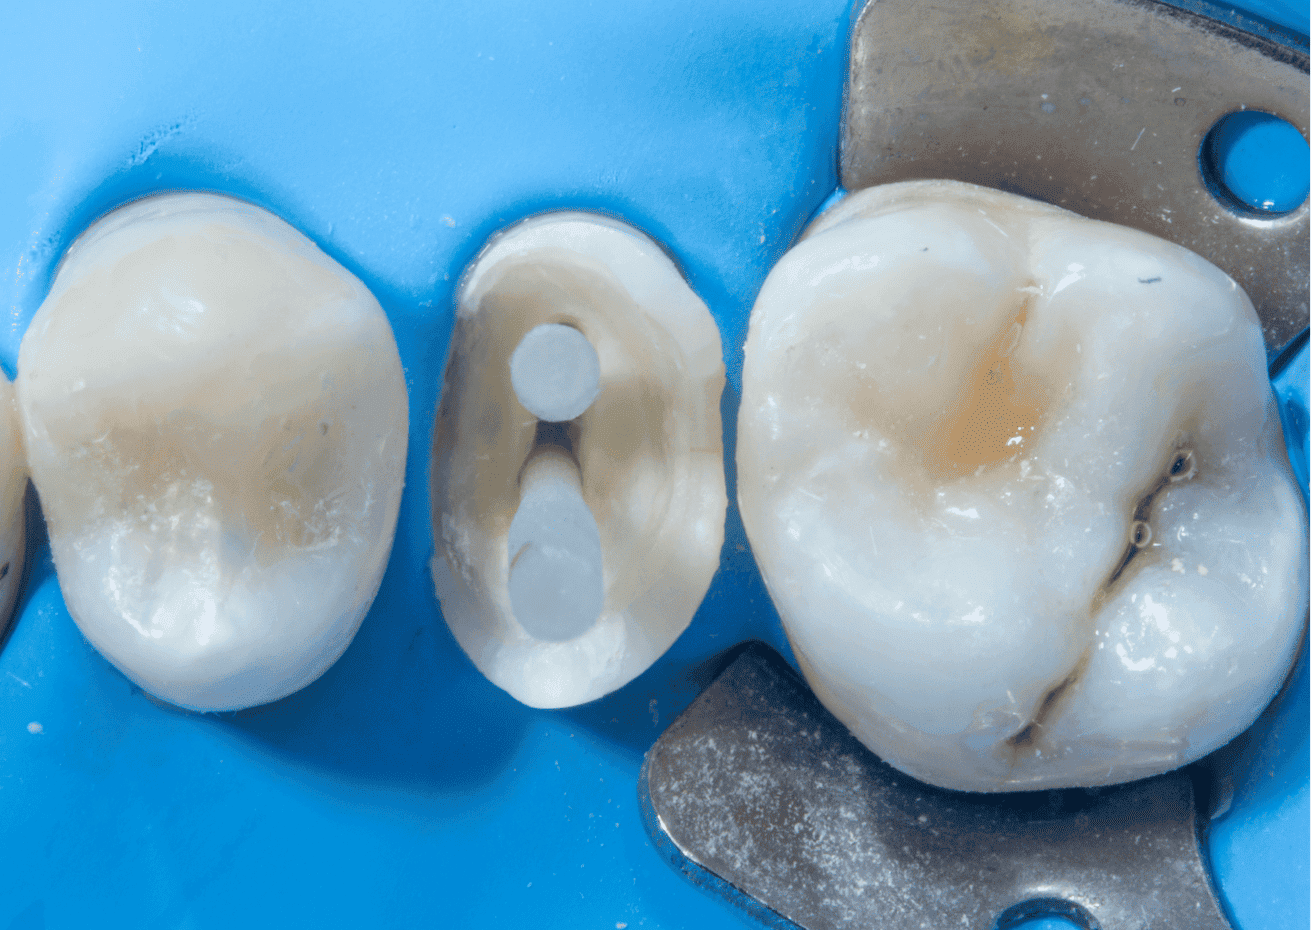

O exame clínico inicial, do dente 15, apresentava selamento provisório com ionômero de vidro e exame radiográfico apresentava alívio de 2/3 do conduto.

No planejamento reabilitador, foi reabilitado com dois pinos Whitepost SYSTEM cimentados com a combinação de sistema adesivo Ambar Universal APS e cimento resinoso dual Allcem CORE, que também foi utilizado para construção do núcleo de preenchimento.